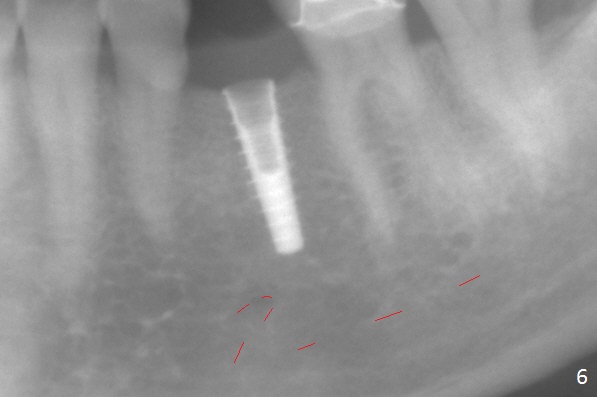

Initial osteotomy with 1.6 mm drill for 11 mm seems to be distal (Fig.1). The trajectory should be changed as shown by the black line in Fig.2; the drawback would be close to the Mental Loop (red line). Fortunately the trajectory is changed, but not so much as to be close the Loop when a 4x11 mm dummy implant is placed (Fig.3). When a 4x13 mm IBS is placed with 46 Ncm, there is clearance from the Loop (Fig.4-6). In fact there is no postop paresthesia. The main point is no block anesthesia. Infiltration anesthesia is administered with 34 mg Xylocaine with 17 mcg Epinephrine. The patient experiences dull pain when the implant is placed (Fig.4-6). After further anesthesia with 68 mg Septocaine, 17 mcg Epinephrine, the implant is torqued for a few turns (still with some discomfort). Finally autogenous bone with Osteogen is placed around the implant following placement of a 4.5x4(2) mm abutment. To reduce anxiety, a shorter implant should have been used. The patient complains of cold sensitivity in the lower left quadrant 4 months postop (Fig.7): the implant apparently close to the Mental Loop. Without an immediate provisional, the gingiva around the abutment is healthy.